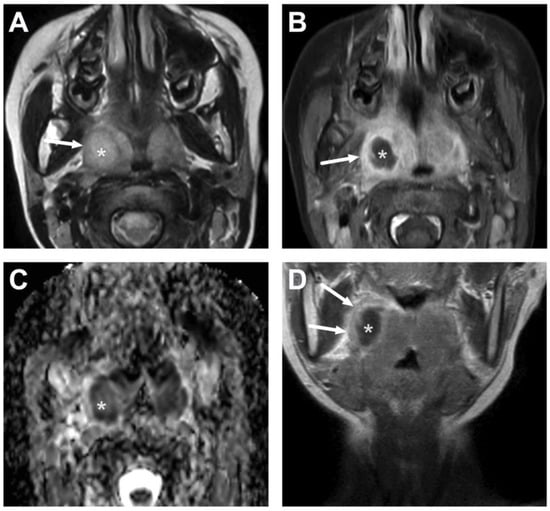

4.2. Retropharyngeal Abscesses and Suppurative Lymphadenitis